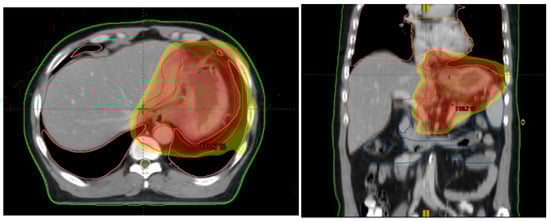

All patients received a CT simulation (16-slice Philips Brilliance CT BigBore, Deventer, The Netherlands) in the supine position with oral and intravenous contrast agents. Bowel preparations were conducted before the CT scan (200 mL liquid to fill the stomach, e.g., water or milk). The clinical target volume (CTV) were contoured on the axial CT slices. The CT scanning range were delineated based on the endoscopy, and CT/MRI or ultrasound results taken into consideration. Involved lymph nodes were defined as short (diameter: >1 cm), or confirmed by diffusion weighted imaging or PET/CT. Gross tumor volumes (GTV) had to be delineated for the primary tumor as well as for the involved lymph nodes. The global clinical target volume (CTV) was calculated by combining the following structures: GTV, GTV lymph node and lymphatic drainage area (lower esophagus, perigastric (D1) and D2 stations), CTV tumor (which was obtained by adding a margin of 1.5 cm to GTV tumor, 0.5 cm to GTV nodal), and the lymphatic spread. The planning clinical target volume (PTV) was the CTV plus 8 mm margin in the craniocaudal direction, and 6 mm in the anteroposterior and left–right directions. The regime consists of a total dose to PTV of 45 Gy in 25 daily fractions of 1.8 Gy five days a week. Radiotherapy plans were generated on the Eclipse treatment planning system (Eclipse Inc., Madison, WI, USA). The planning goals were delivering at least 95% of the prescribed dose to 95% of the PTV. Dose prescription and recording complied with the recommendations of the ICRU 50/62 (International Commission on Radiation Units and Measurements, ICRU) []. Daily patient set-up was performed using laser alignment to reference marks on the skin of the patient. CBCT was used for image guidance before each day’s treatment delivery. Using soft tissue registration, if the filling of the stomach did not meet the image positioning requirements, it was necessary to suspend the current treatment and restart the treatment after meeting the accuracy of the location. Patients were repositioned after co-registration of CBCT images with the planning CBCT images (see Figure 2 as an example).

Figure 2.

Example of image-guided radiotherapy.